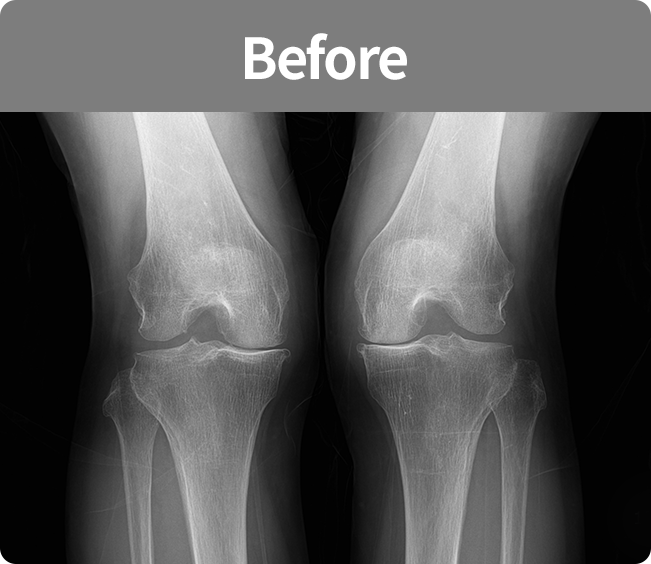

인공 관절 치환술

퇴행성관절염 및 기타 관절손상으로 통증이 심해

정상생활을 할 수 없고 다른 치료나 시술로 효과가 없는 경우에 시행하는 수술법(부분 치환술, 전 치환술)